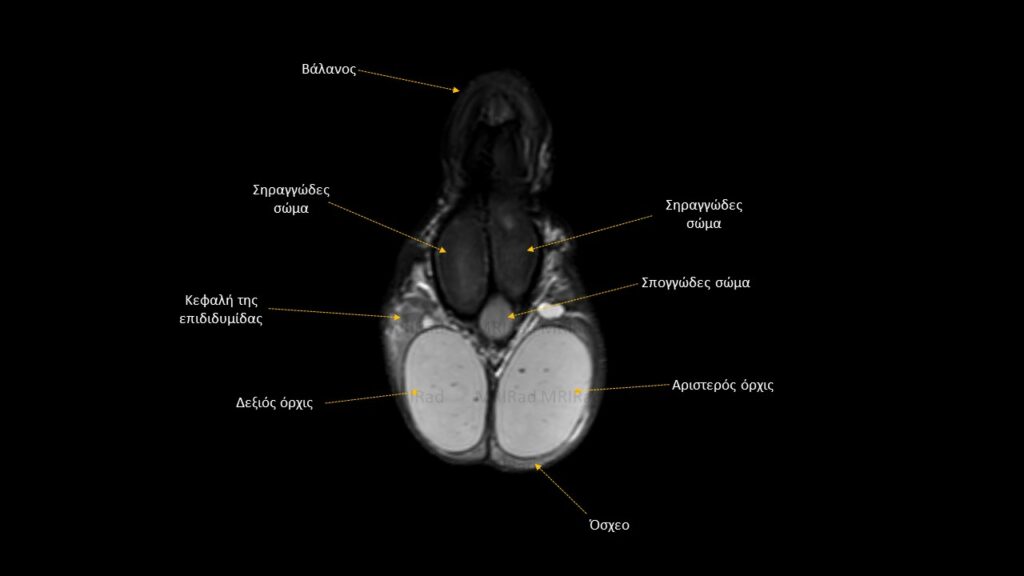

Βασική Ακτινοανατομία MRI Οσχέου